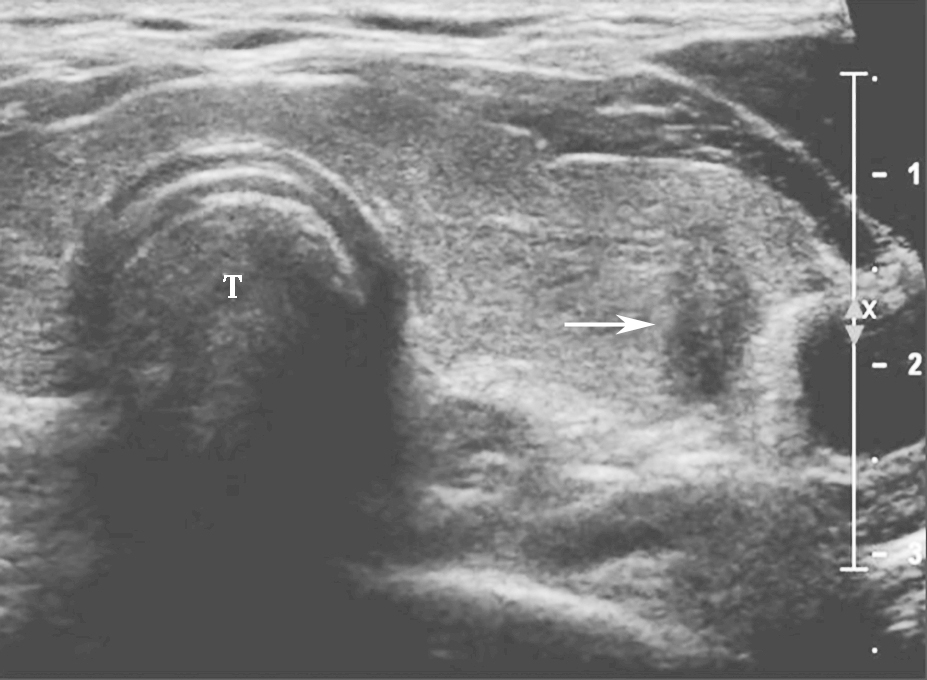

(十)甲状腺滤泡癌

甲状腺滤泡癌和滤泡腺瘤在超声上鉴别有一定困难,即使是FNA细胞学也很难鉴别。但有报道认为:与甲状腺乳头状癌不同,甲状腺滤泡癌常为等回声或高回声,微小钙化很少见,病变多伴有厚薄不一的低回声晕或者局部低回声晕。彩色多普勒血流信号丰富也是该类病变的特点之一(图11、图12)。

:内部回声不均伴厚薄不一低回声晕.jpg)

图11右侧颈部纵切面:甲状腺右叶中部中等回声(箭头所示):内部回声不均伴厚薄不一低回声晕

:中等回声彩色多普勒血流信号丰富而杂乱.jpg)

图12右侧颈部纵切面(与图3-3-11同患者、同切面):中等回声彩色多普勒血流信号丰富而杂乱